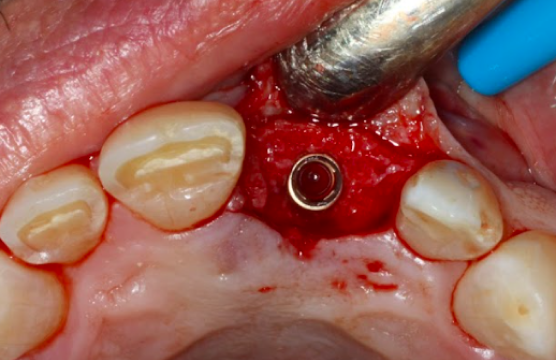

Surgical Site Preparation Process

Socket Preservation for implant

3 Months

3 Months

Implant 21

Surgical Site Preparation Process

Socket Preservation for implant

Socket Graft of 21: 3 Months

Implant 21